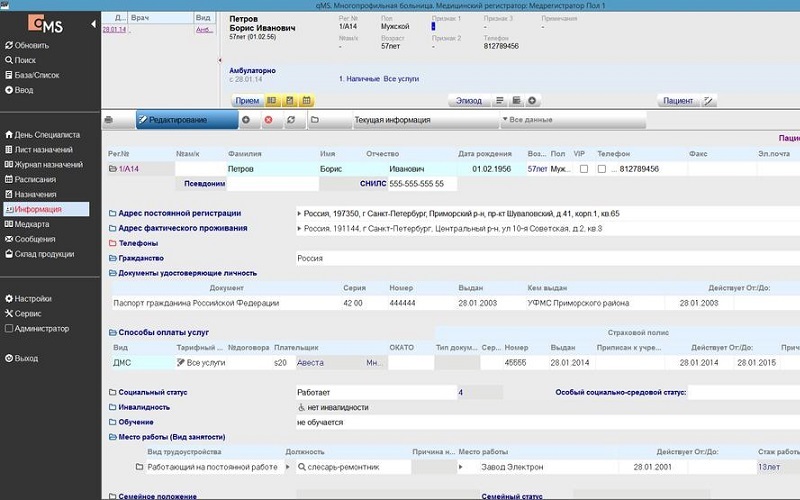

Визуальное сравнение

автоматизации технологических процессов современной медицинской лаборатории и поддержки всех видов лабораторных исследований.

Смотреть отзыв →«Система страдает множеством серьёзных недостатков: Интерфейс абсолютно недружелюбный и интуитивно непонятный. Экран перегружен лишними иконками и кнопками, которые отвлекают врача и не несут практической ценности. …»

Смотреть отзыв →Интерфейс